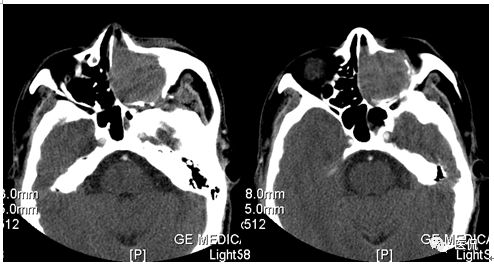

增强动脉期

CT平扫及增强示:左侧上颌窦及鼻腔可见软组织密度影,呈膨胀性生长,周围骨质压迫性吸收破坏,累及左眶,病灶密度不均匀,周边区可见点状钙化,增动脉期轻度强化,局部见小灶性稍高密度区,静脉期病灶内见不均匀明显强化,CT值最高达117HU,延迟期强化范围有所增大。

本例病灶较大,周围骨质可见吸收破坏,并累及眼眶,病灶内少量钙化,增强扫描具有一定特征性,表现为动脉期轻度强化,局部见小灶性稍高密度区,静脉期病灶局部呈明显强化,CT值最高达117HU,延迟期强化范围有所增大,呈延迟渐进性强化的特点,推测为病灶内出血所致。